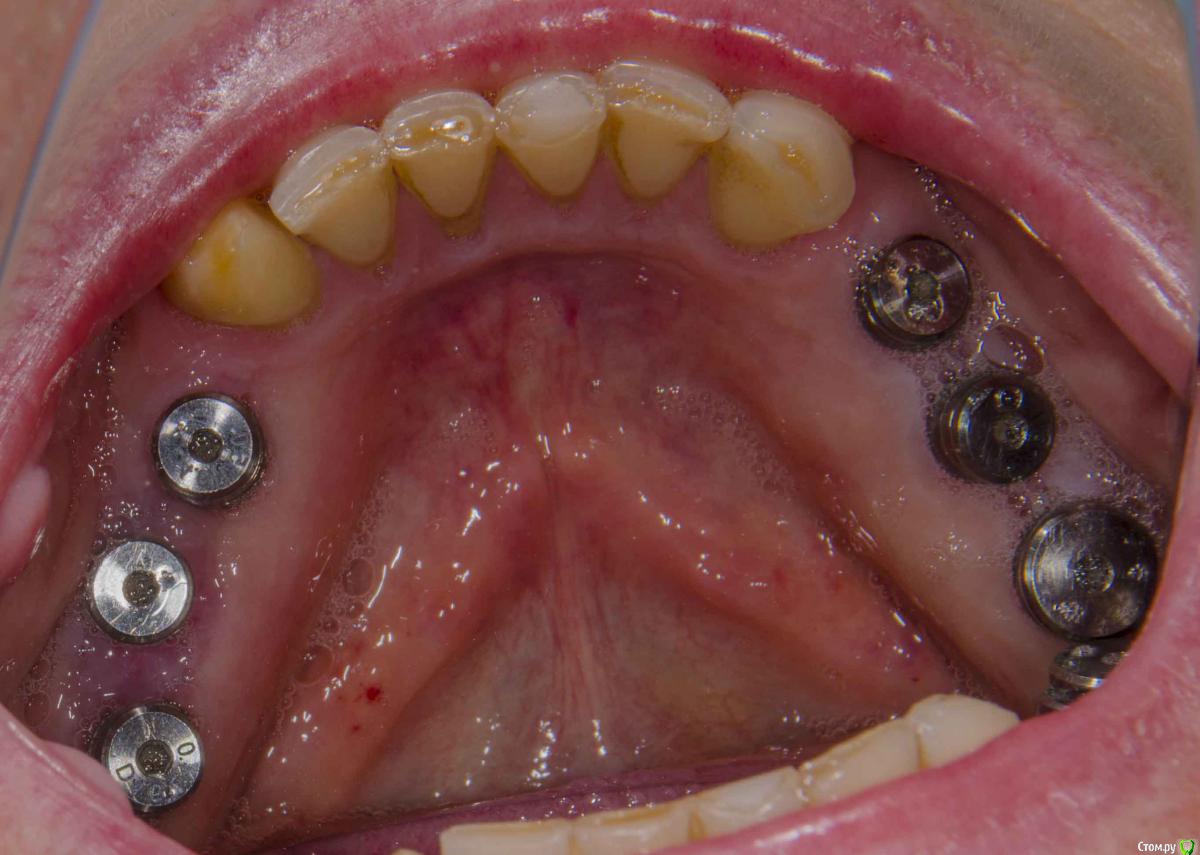

kamranchick Опубликовано 20 декабря, 2015 Поделиться Опубликовано 20 декабря, 2015 (изменено) Добрый день уважаемые форумчане, с наступающим друзья.хотелось бы спросить у Вас, частенько на этапе раскрытия сталкиваюсь с непонятными моментами, а именно, на НЧ иногда когда ушиваю рану получается вот так какая картинатам где не зашивали, картина выглядет более лучше чем там где зашивали)1 этап осмотр через 5 дней. и снятие швов2 этап осмотр через 2 неделиИзвините за качество фото, не умею фотографировать, вскоре этот недуг будет исправлен.Как Вы раскрываете имплантаты если они стоят рядом? точечно или как то по другому?ps работа была произведена давно, теперь там далеко от зубов не отступаю) Изменено 20 декабря, 2015 пользователем kamranchick Ссылка на комментарий

andrey_1965 Опубликовано 21 декабря, 2015 Поделиться Опубликовано 21 декабря, 2015 Нормальные фото,что надо- то видно.После раскрытия пробуйте полулунно сделать вырез под формирователи-будете меньше тянуть для сближения.Опять же вырезки можно при необходимости пристроить. Для закрытия "встык" без мобилизации в какой-то степени не обойтись.Конечно, хочется чуть ли не сосочки сразу чтоб.Кто ж не хочет.Не переживайте,на временных доформируете-все будет симпатично.Успехов! 1 Ссылка на комментарий

kamranchick Опубликовано 22 декабря, 2015 Автор Поделиться Опубликовано 22 декабря, 2015 (изменено) А какими швами рекомендуете фиксировать лоскуты?в Соседней ветке Карэн тоже узловые наложил)) либо дело в толщине. Изменено 22 декабря, 2015 пользователем kamranchick Ссылка на комментарий

andrey_1965 Опубликовано 22 декабря, 2015 Поделиться Опубликовано 22 декабря, 2015 А какими швами рекомендуете фиксировать лоскуты?в Соседней ветке Карэн тоже узловые наложил)) либо дело в толщине.Дело не столько в типе шва,сколько в рефлекторном желании свести " встык",неизбежен "перетяг" при установки ФДМ таких размеров.Если так непреодолимо стремление к абсолюту- то что мешает бережно поискать заглушки трансгивгивально,затем стандартный формирователь-расширяющий формирователь-временная коронка?Сложно,кто б спорил,зато прикрепление цело и шить не надо. Ссылка на комментарий

Acidrocker Опубликовано 22 декабря, 2015 Поделиться Опубликовано 22 декабря, 2015 А какими швами рекомендуете фиксировать лоскуты?в Соседней ветке Карэн тоже узловые наложил)) либо дело в толщине.Обычными узловыми. Если матрасные - то точки вкола и выкола должны быть максимально близко друг к другу. Ссылка на комментарий